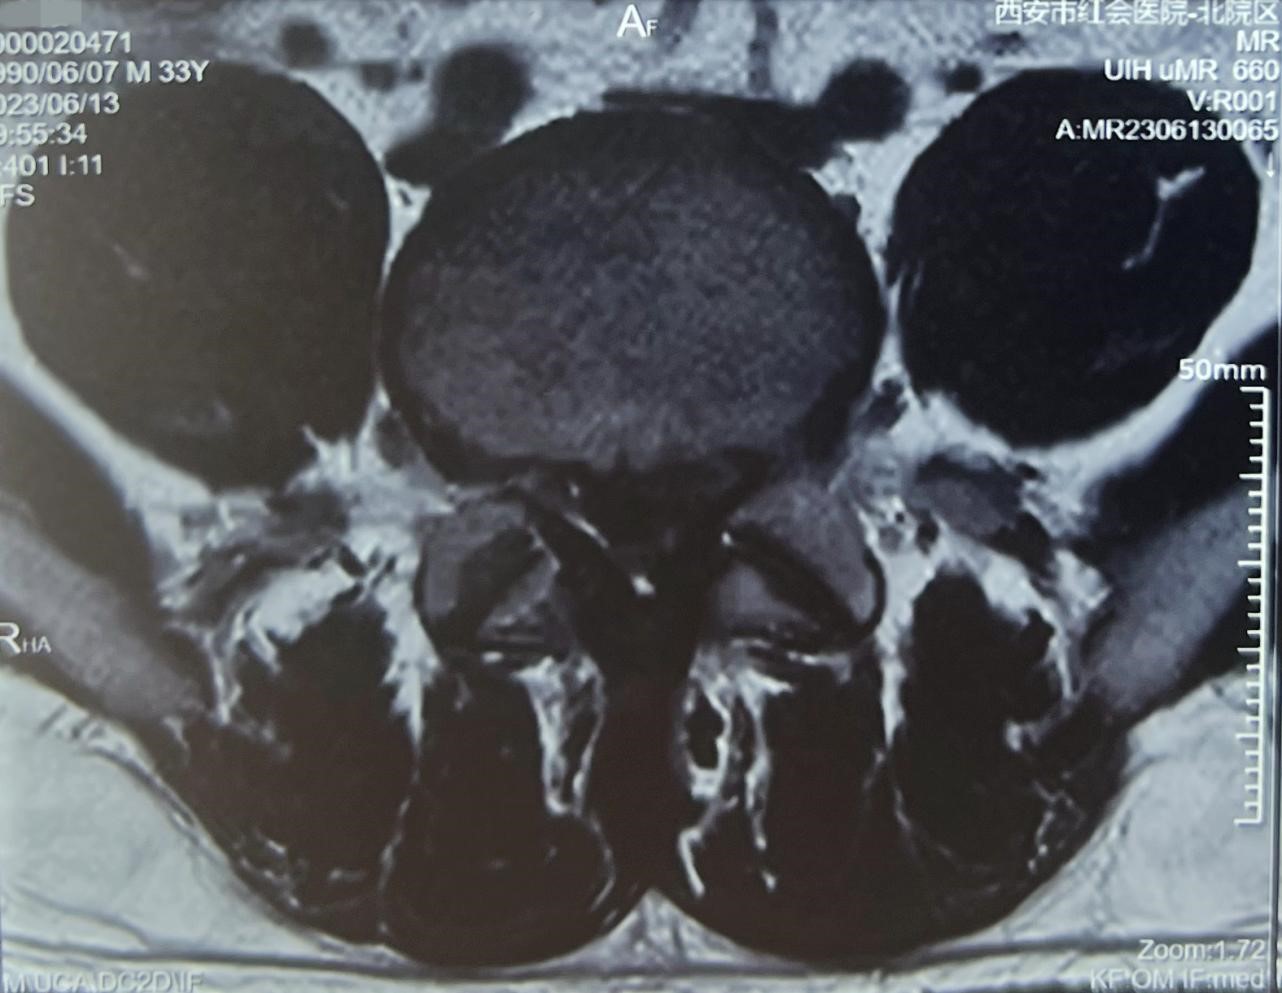

患者术前影像检查资料

患者就诊后,影像学检查显示腰4-5和腰5骶1两个节段均存在突出。其中腰4-5椎间盘突巨大突出,双侧神经根受压。